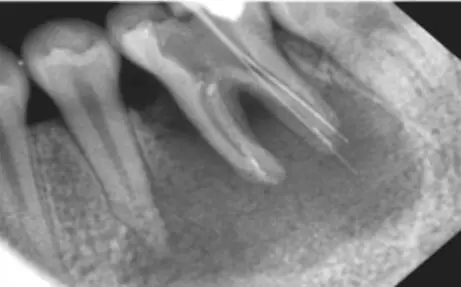

看下圖X光片是不是覺得欠充了呢?

其實:X光片確定長度經(jīng)常性引起超充?

X線片法缺陷

1) 三維結構投射在二維平面上,因投射角度不一樣,數(shù)據(jù)容易出錯。

2)根尖孔不能體現(xiàn)在牙片上,而80%以上的根尖孔都不在牙齒根尖而是在側邊。

根尖開口在側邊時,X線片投射引起長度偏差錯誤。

根尖開口距離牙齒根尖距離越大,誤差越大,會引起嚴重超充。